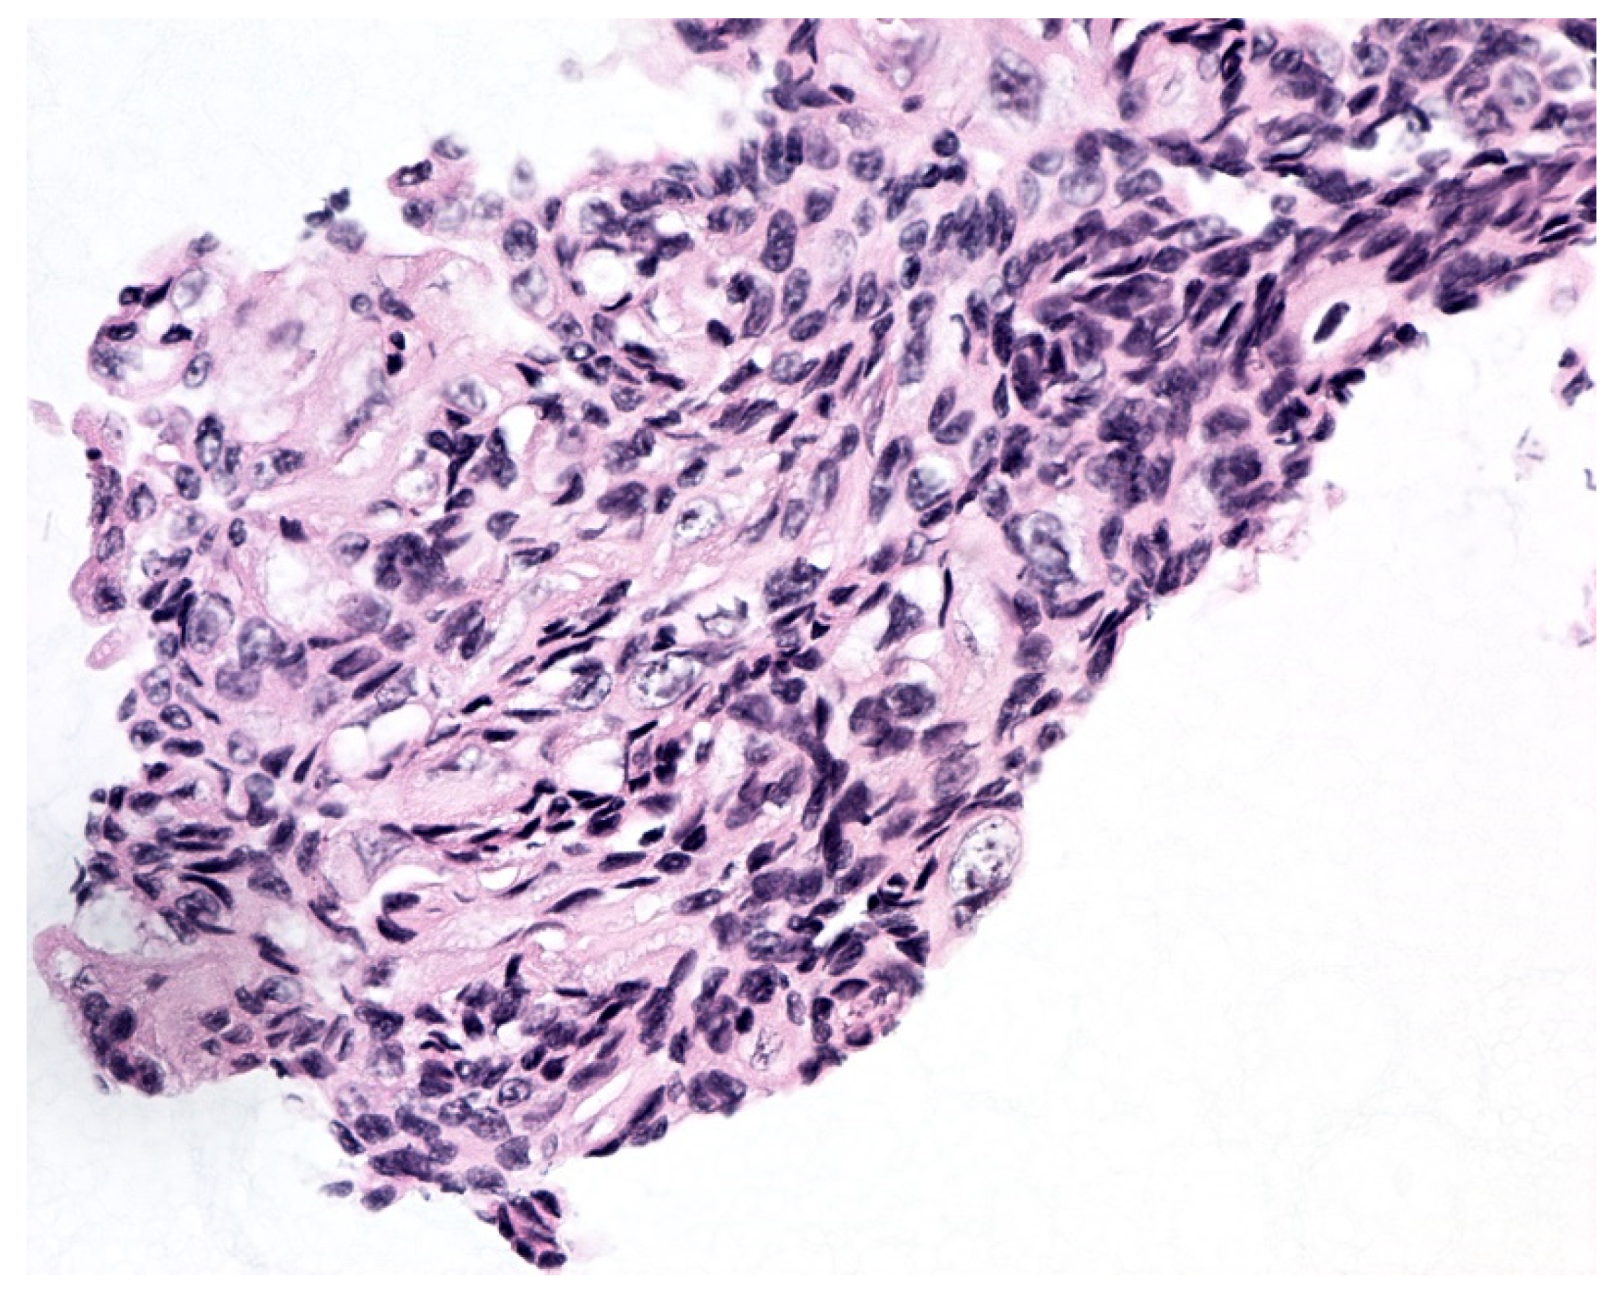

| Morphology | Differential Diagnosis | Helpful Distinguishing Features |

| Bland-appearing urothelial tissue fragments (BUTFs) lacking fibrovascular cores Note: Regardless of whether the BUTFs in question represent LGUN or benign urothelium, they would be classified under the NHGUC category according to TPS. | Benign urothelium |

| LGUN |

| Bland-appearing urothelial tissue fragments with fibrovascular cores Note: While UTFs with fibrovascular cores lacking atypical features usually represent LGUN, some HGUCs can be seen as a monotonous population of cells and/or have paradoxically hypochromatic nuclei. If HGUC cannot be excluded, an indeterminate TPS category can be used. | LGUN |

| HGUC |

| Atypical-appearing urothelial tissue fragments (AUTFs) lacking fibrovascular cores Note: Some LGUN lesions may produce cells with increased pleomorphism than is typically seen. Thus, some AUTFs classified into indeterminate categories may end up representing LGUN. | Stone atypia |

| Atypical-appearing urothelial tissue fragments (AUTFs) with fibrovascular cores Note: Some LGUN lesions may produce cells with increased pleomorphism than is typically seen. Thus, some AUTFs classified into indeterminate categories may end up representing LGUN. | LGUN |